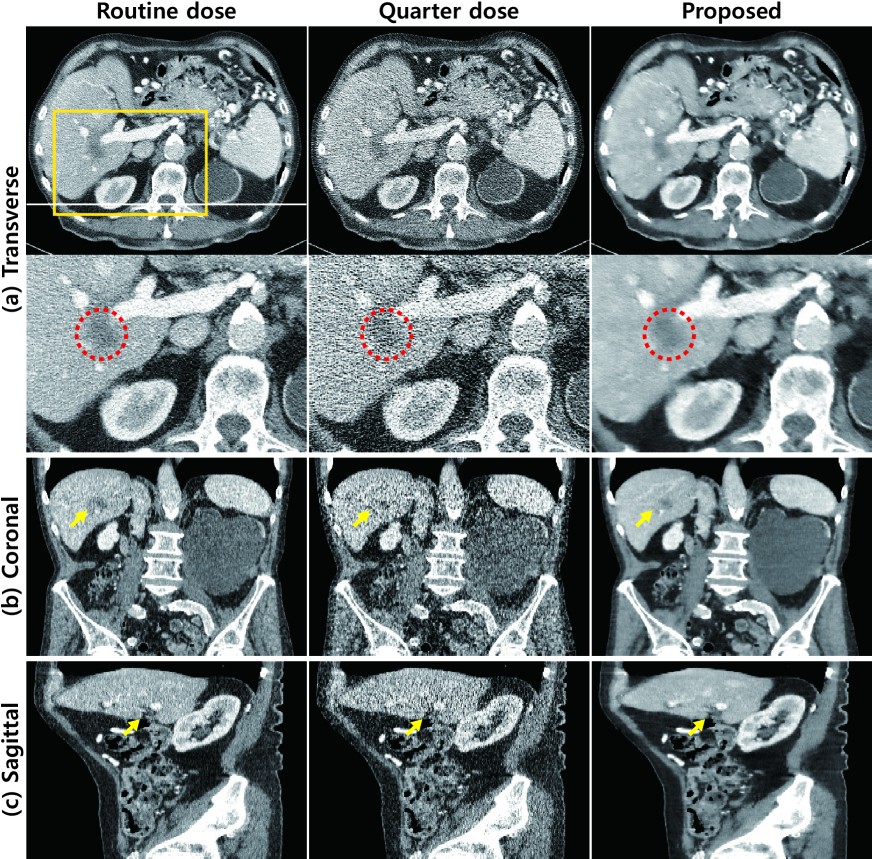

Refer to caption

Figure 8: X-ray CT images from training data set ‘L506’. Routine-dose images are in the first column, quarter-dose images are in the second column, and denoised images using the proposed algorithm are in the third column. (a) Transverse images. Enlarged images within the yellow box in the second row. The lesion is marked by red dashed circles. (b) Coronal images and (c) Sagittal images. The intensity range was set to (-160,240) [HU] (Hounsfield unit).

For a subjective evaluation, Fig. 8 shows the denoised images from the data set of one patient with a normal-dose and a quarter-dose. Organs such as the liver can be seen in these images. The results of the proposed network preserved the textures of the liver such that a better determination of the location of the lesion was possible, as highlighted by the red dashed circle. The coronal and sagittal presentation of the results is also shown in Fig. 8. Yellow arrows indicate the regions with high noise levels. The proposed network can remove a wide range of noise levels while maintaining the edge information.